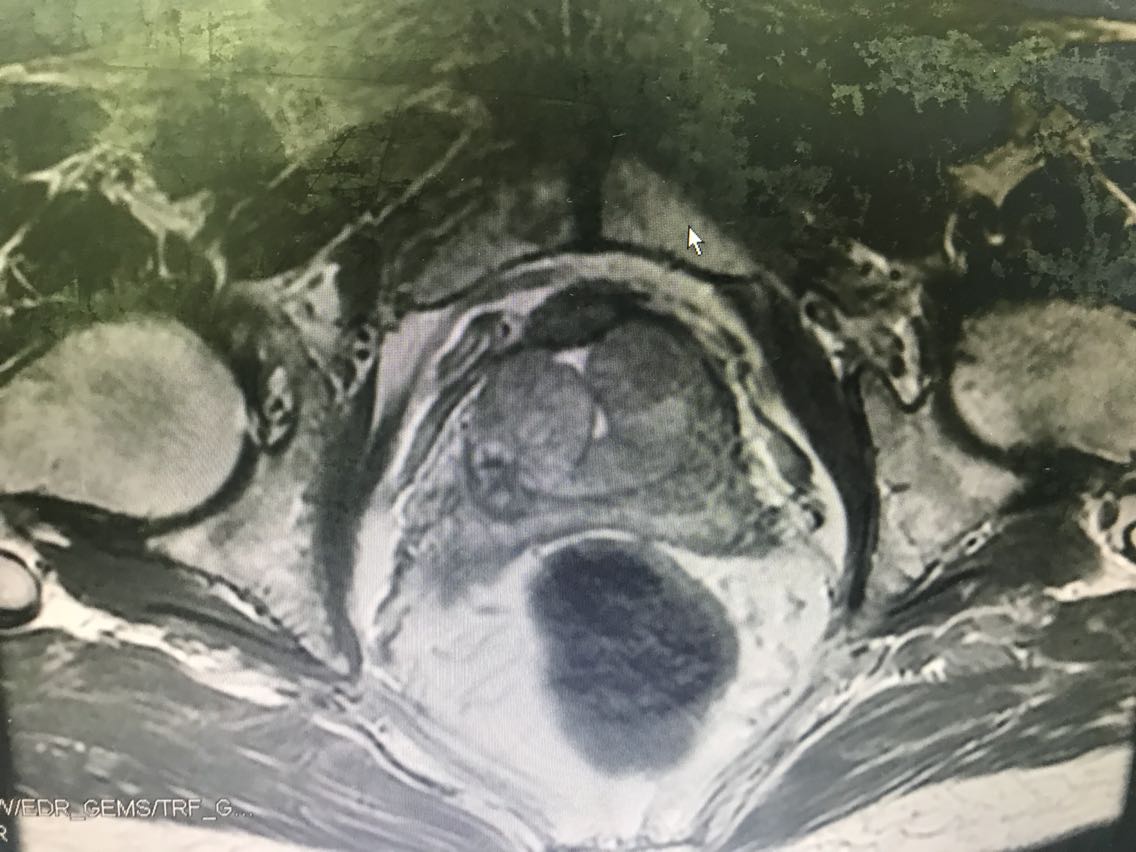

患者男性,77岁。 主诉:血尿7+月 现病史:入院前7+月,患者出现血尿,于外院体检查示PSA升高(10.62),服药血尿控制(具体药物不详),无尿频、尿急、下腹疼痛等不适,为求进一步诊治于我院门诊就诊,查前列腺MRI:前列腺尖部右侧中央带结节及9-10点结节,多系前列腺癌。门诊行前列腺穿刺活检示:编号1、2、3、4、5、6查见前列腺腺癌,Gleason评分4+3=7分。门诊以“前列腺癌”收入我科。患病来精神、睡眠、食欲可,大小便无异常,体重无明显变化。 既往史无特殊。

查体:腹部平软,无压痛及反跳痛,双肾及输尿管走行区无压痛,肾区无叩痛。直肠指检:前列腺Ⅱ°大,双侧质硬,右侧叶扪及约1cm硬结。 辅助检查: 前列腺MRI(2018-6-14,本院):前列腺尖部右侧中央带结节及9-10点结节,多系前列腺癌,累及右侧外周带 前列腺穿刺活检示(2018-6-28,本院):编号1、2、3、4、5、6查见前列腺腺癌,Gleason评分4+3=7分。